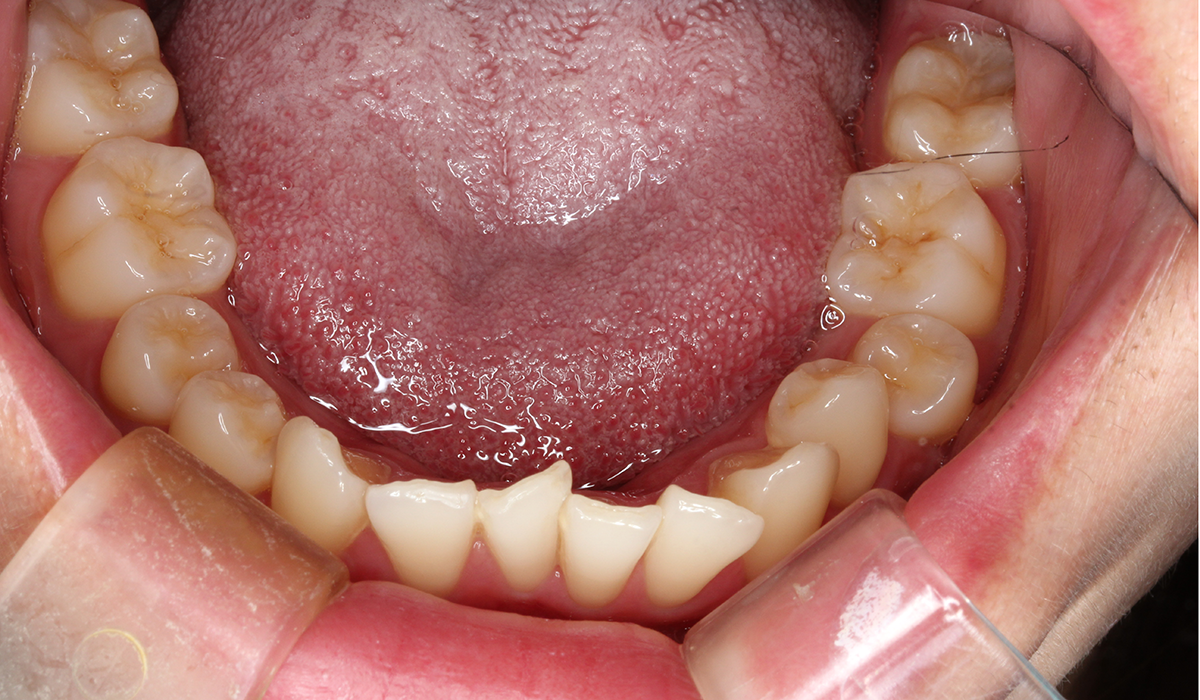

下顎

術前

BK終了時

術後